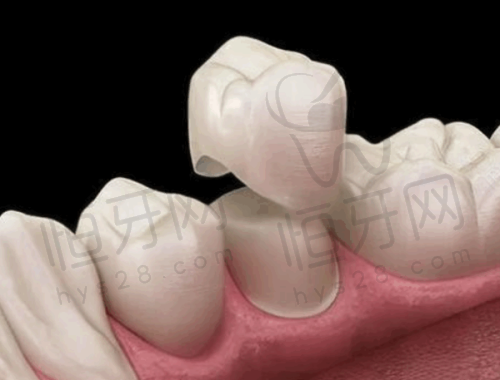

美学修复中 心:如果牙齿有缺损、变色等问题,美学修复可以让牙齿修复美丽。全瓷修复是该中 心的特色项目之一,全瓷材料具有良好的生物相容性和美观性,修复后的牙齿几乎可以以假乱真。

患者C:“我之前牙齿有缺损,在这里做了全瓷修复。修复后的牙齿非常美观,而且特别坚固。医院的设备特别精良,消毒也特别严格,让我特别放心。以后有口腔问题还会来这里。”